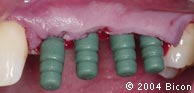

42. | 绿色的3.0mm塑料印模柱插入3.0mm的种植体内径,准备取种植体水平转移印模。 |

43. | 轻敲印模柱使其就位。 |

44. | 在印模柱周围注射印模材料,取种植体水平转移印模。 |

45. | 取模后的四根绿色塑料印模柱。 |